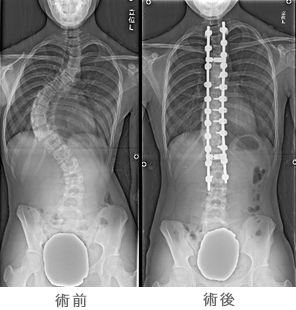

脊柱側弯症に対する矯正手術

側弯症の大部分は学童期の後半から思春期に発生します。側弯症では脊柱が横(側方)に曲がり、進行すると変形による心理的ストレスの原因や腰痛や背部痛、肺活量の低下などの呼吸機能障害、まれに神経障害を伴うことがあります。手術は曲がった脊柱を矯正固定する方法が行われます。背中から行う方法(後方法)と体の横から行う方法(前方法)があり、患者さんの年齢、側弯の部位、大きさ、タイプなどを考えて、いずれかあるいは両者が行われます。和歌山県立医科大学整形外科では、手術に伴う神経麻痺を防ぐための脊髄機能モニタリングや自己血輸血を導入することで手術の安全性を高めています。手術方法により異なりますが、概ね1週以内に装具を装着することなく歩行ができ、2−3週以内で退院可能となります。脊柱側弯症についてさらなる詳しい知識を望まれるかたは日本側彎症学会ホームページもご参照下さい。

側弯症の大部分は学童期の後半から思春期に発生します。側弯症では脊柱が横(側方)に曲がり、進行すると変形による心理的ストレスの原因や腰痛や背部痛、肺活量の低下などの呼吸機能障害、まれに神経障害を伴うことがあります。手術は曲がった脊柱を矯正固定する方法が行われます。背中から行う方法(後方法)と体の横から行う方法(前方法)があり、患者さんの年齢、側弯の部位、大きさ、タイプなどを考えて、いずれかあるいは両者が行われます。和歌山県立医科大学整形外科では、手術に伴う神経麻痺を防ぐための脊髄機能モニタリングや自己血輸血を導入することで手術の安全性を高めています。手術方法により異なりますが、概ね1週以内に装具を装着することなく歩行ができ、2−3週以内で退院可能となります。脊柱側弯症についてさらなる詳しい知識を望まれるかたは日本側彎症学会ホームページもご参照下さい。